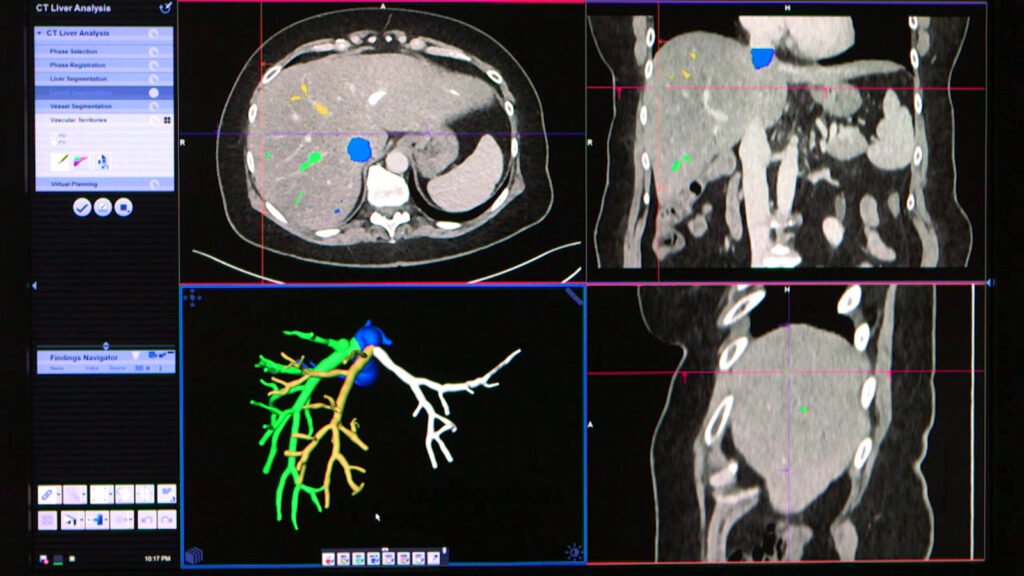

Syngo: análisis avanzado y volumetría

Soporte para mediciones y análisis orientados a oncología y vascular, mejorando reproducibilidad para estadificación y seguimiento.